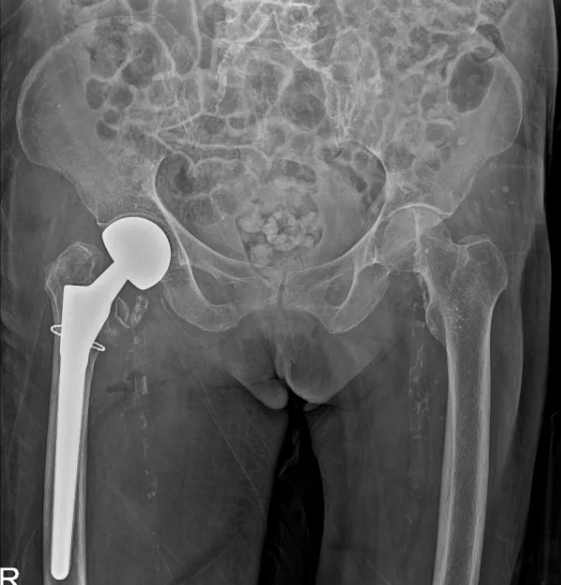

完成人工股骨头置换术

考虑到患者年事已高,若选择保守治疗,长期卧床将极大增加肺炎、深静脉血栓及压疮等并发症的风险;而手术治疗则因患者合并严重冠脉病变,麻醉及手术过程中的风险显著增加。经过全面的营养支持和血压调控,心血管内科、麻醉手术中心进行了详尽的术前评估。心血管内科苏波主任医师团队先行冠脉造影术,确认冠脉严重狭窄后,立即实施了支架置入术,稳定了病情。术后当日,程建文主任医师团队紧接着进行了右侧人工股骨头置换术,手术过程顺利,术中出血量控制在百毫升左右。术后,患者被转入外科重症监护室进行密切观察,次日即转回普通病房,生命体征平稳,恢复迅速。